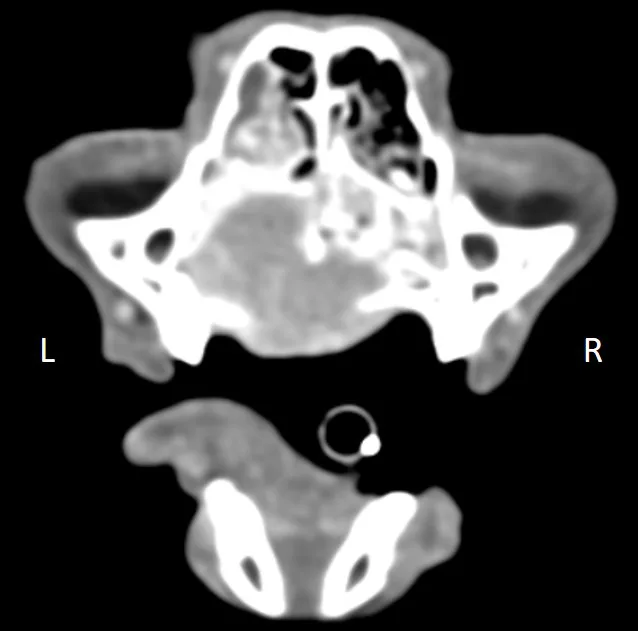

CT of the nasal cavity can help determine extent and location of disease, presence or absence of turbinate erosion, involvement of sinuses and surrounding tissues (eg, lymph nodes), dental arcade involvement, presence of some types of foreign material, and integrity of the cribriform plate (Figure 2); it can also guide sample acquisition and treatment planning. CT can be performed with the patient under heavy sedation, but general anesthesia may be preferred, depending on scanning time required and whether additional procedures are planned.

CT scan of nasal passage in a cat.

FIGURE 2

Nasal CT image of a 12-year-old neutered male domestic shorthair cat with a heterogeneous contrast-enhancing mass in the left nasal passage and extension into the right nasal passage causing bony destruction of the hard palate and nasal septum